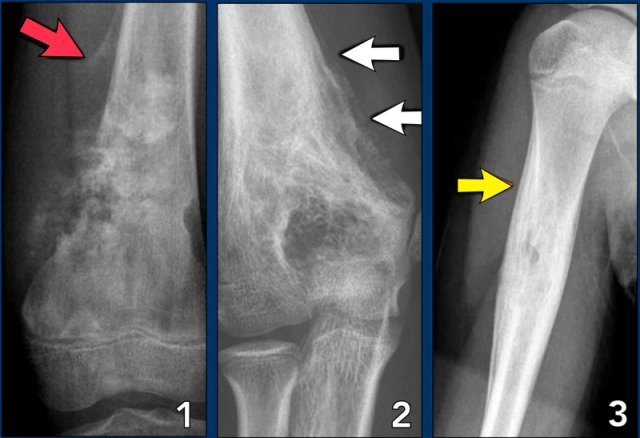

Aggressive periosteal reaction (2)

- Osteosarcoma with interrupted periosteal rection and Codman's triangle proximally (red arrow).

There is periosteal bone formation perpendicular to the cortical bone and extensive bony matrix formation by the tumor itself. - Ewing sarcoma with lamellated and focally interrupted periosteal reaction. (white arrows)

- Infection with a multilayered periosteal reaction.

Notice that the periostitis is aggressive, but not as aggressive as in the other two cases.